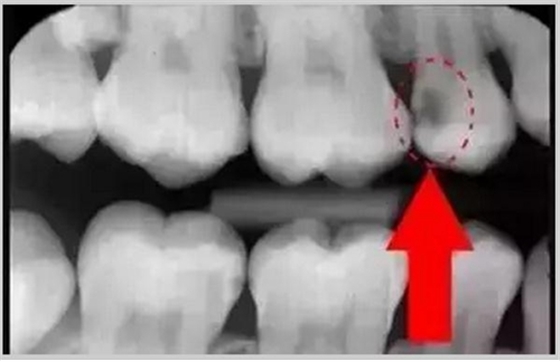

從上圖中可以知道除了外層的一點牙釉質(zhì),牙齒里面出了問題,肉眼是無法觀察到的。牙醫(yī)不長透視眼當然不能透過現(xiàn)象看到牙齒本質(zhì)嘍。因此,為了對牙齒進行全面的了解,拍個牙片還是很有必要的。

圈出來的地方或多或少都有點齲齒,但是有些你并不能看見。這些齲齒還淺不會讓你有什么感覺,頂多吃東西塞牙,和冷水敏感而已。

暗的部位說明齲齒已經(jīng)非常嚴重了!

上面這個是接近牙髓了!